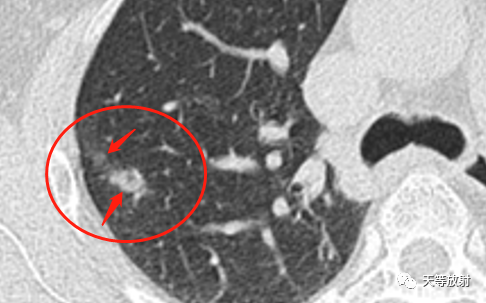

这个层面出现囊腔+实性结节,囊壁较厚。